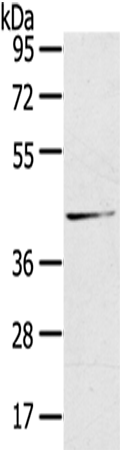

分类: 科研抗体货号: P11853别名: SYNII; SYNIIa; SYNIIb应用: WB,IHC反应种属: Human, Mouse, Rat